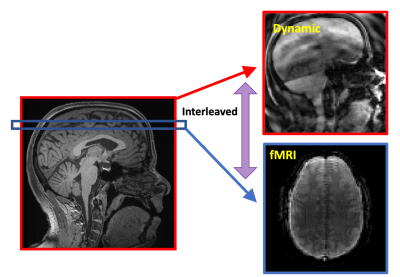

The Partial Separability (PS) model acquires a temporal navigator at each time point and then only one shot of the imaging data that highly undersamples (k, t)-space. After the temporal basis is determined from the temporal navigators with very high temporal resolution, the corresponding spatial basis of the PS model can be determined from the sparsely sampled imaging data across the time series. For this work, we designed a navigator that was one shot of a 24-shot, 64-matrix size spiral-in navigator. This was immediately followed by acquiring one shot of a 24-shot, 128-matrix size spiral-out imaging data. The navigator and imaging readouts were concatenated together as shown in Figure 1. SimulScan proceeds by acquiring one of these dynamic shots in between each 2D functional MRI slice (see Figure 2). The fMRI was a spiral-in, TE = 25 ms, 96 matrix size trajectory with a reduction factor of 2, reconstructed by SENSE5,6. We used a 38-slice fMRI acquisition with 3 mm slice thickness, fat sat on, resulting in an overall TR (fMRI slice and dynamic shot) of 76.6 ms, 13 fps dynamic imaging, and an overall TR for 38 slice fMRI data of 2.9 s. A healthy adult subject was scanned for 9.5 minutes and asked to tap their tongue several times during the course of the run, without cue and at their own pace, trying to get at least 20 taps in the run.

Figure 2: Setup of the SimulScan Acquisition with 1 mid-sagittal dynamic imageand 38 functional MRI slices. The acquisition interleaves a functional slice with the dynamic imaging. Note the dark line in the middle of the fMRI axial slice corresponding to the dynamic imaging plane.